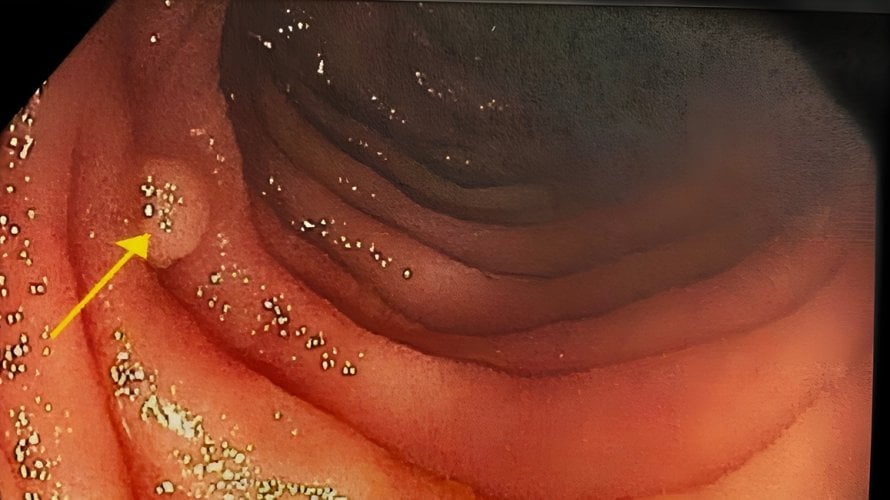

Peutz‑Jeghersov sindrom rijedak je nasljedni poremećaj koji primarno zahvaća probavni sustav. Ovaj sindrom karakterizira pojava brojnih dobroćudnih polipa u probavnom traktu te specifičnih tamnih pigmentiranih mrlja na koži i sluznicama, osobito oko usana, u ustima i na prstima. Iako su polipi koji se javljaju kod ovog sindroma najčešće benigni, osobe s ovim stanjem imaju povećan […]